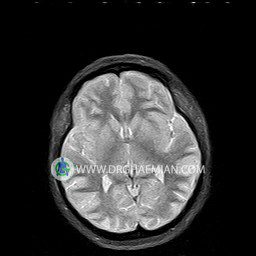

پزشکان اغلب از تصویربرداری ام آر آی برای تشخیص و درمان عارضه های پزشکی که فقط با استفاده از اشعه ایکس یا میدان مغناطیسی و امواج رادیویی قابل مشاهده است، استفاده می کنند. دستگاه ام آر آی تصاویر دقیق از ساختار های داخلی بدن ایجاد می کند. در این کیس نوریت اوربیت چب و سلای خالی بیمار مشاهده می شود.

– Small fluid around the left optic nerve with mild edema suggestive for left optic neuritis

– Extension of suprasella cistern to sella with thin pituitary gland in floor of sella ( empty sella )

are seen